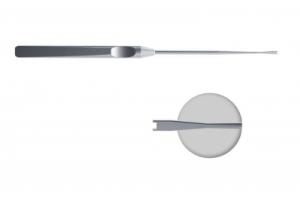

- ID: 0052235

- Артикул: AS-01400-1

Ножницы эндоскопические с одной подвижной браншей (клювовидные, прямые)

- ID: 0052236

- Артикул: AS-01402-1

Ножницы эндоскопические с одной подвижной браншей (клювовидные, правые)